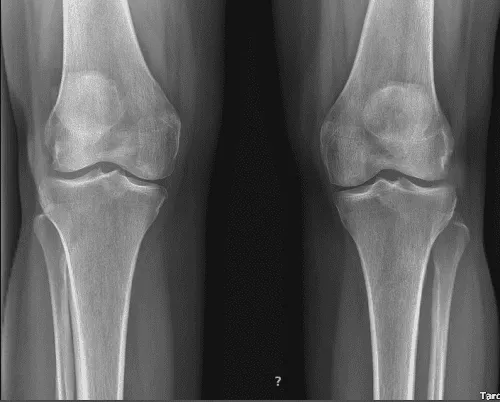

Toma paracetamol, que ayuda. El resultado de la radiografía se presentó hoy y mostró claramente que sus rodillas bilaterales presentan osteoartritis leve en el compartimento patelofemoral y un derrame articular pequeño.

El paciente volvió a nuestra consulta una semana después de la visita inicial. Presenté radiografías bilaterales. La rodilla izquierda muestra pequeños defectos cartílagos de grosor total en la parte medial con el aspecto inferior de las facetas rotulianas laterales y edema subyacente parcheado de médula ósea subcondral.